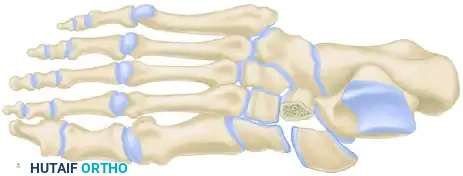

Myerson Classification

Classification facilitates communication and helps determine the vector of displacement, though it is not strictly prognostic. Myerson’s modification of the original Quénu and Küss classification is the academic standard:

- Type A (Total Incongruity): Displacement of all five metatarsals, with or without a fracture of the second metatarsal base. Displacement is typically lateral or dorsolateral, moving as a single unit (homolateral).

- Type B (Partial Incongruity): One or more articulations remain intact.

- Type B1: Medial displacement, often involving the intercuneiform or naviculocuneiform joint.

- Type B2: Lateral displacement, which may involve the first metatarsal-cuneiform joint.

- Type C (Divergent): The first metatarsal displaces medially while the lesser metatarsals displace laterally.

- Type C1: Partial divergent.

- Type C2: Complete divergent. These are high-energy injuries associated with massive soft tissue swelling and a high risk of compartment syndrome.